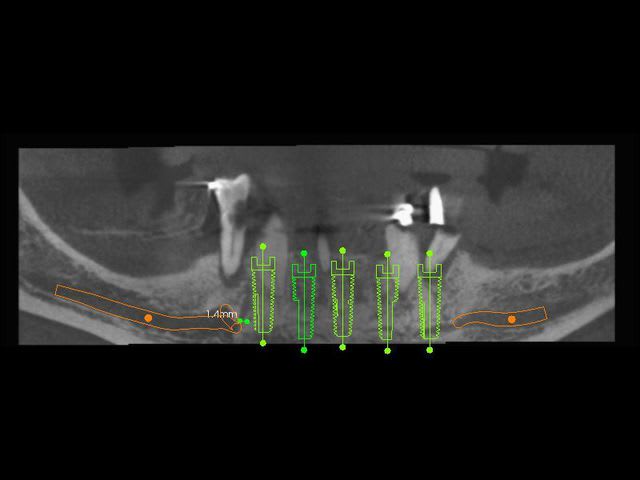

Ce matin j'ai fait la pose de 5 implants symphysaires en extraction implantation immédiate.

Je trouve que les implants sont tous quasiment sur une même ligne car l'arcade n'est pas assez courbe dans le secteur antérieur.

Le problème est que l'émergence des mentonniers se fait en dessous des 4.

Le vrai problème vient du fait qu'il a ses foramina au dessus des 4 et pas des 5 comme on le retrouve habituellement.